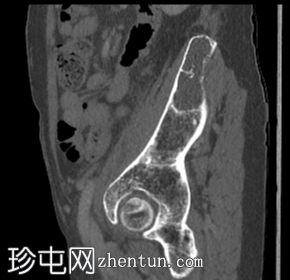

矢状位

骨窗

左侧髂骨内边界清晰的病灶

薄层硬化环

皮质变薄

轻微骨膨胀

内部密度低于肌肉和少量脂肪

薄骨间隔

无骨外软组织肿块